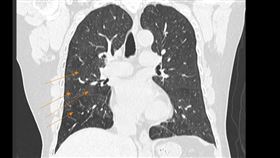

婦頻打破杯盤 竟是肺癌轉移腦作怪

不可輕忽肺癌家族化!台中烏日一名71歲翁姓婦人近期經...